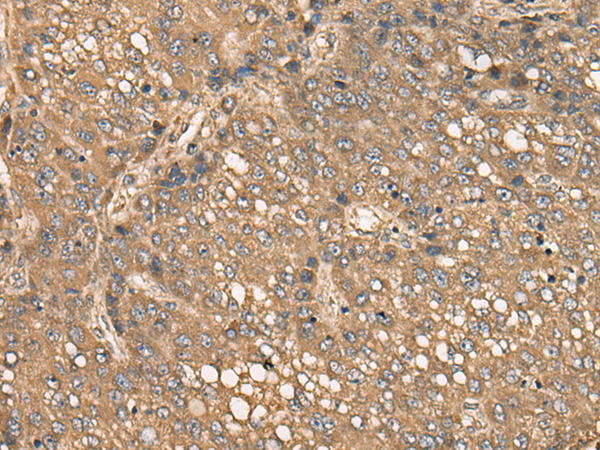

分类: 科研抗体货号: P02429别名: C1orf93; FAM213B应用: WB,IHC反应种属: Human, Mouse, Rat